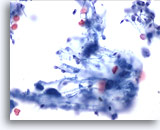

Lavage du bassinet, négatif

Les lavages avec 50 ml de solution saline avant la manipulation de la vessie donnent généralement des échantillons riches en cellules.

20x